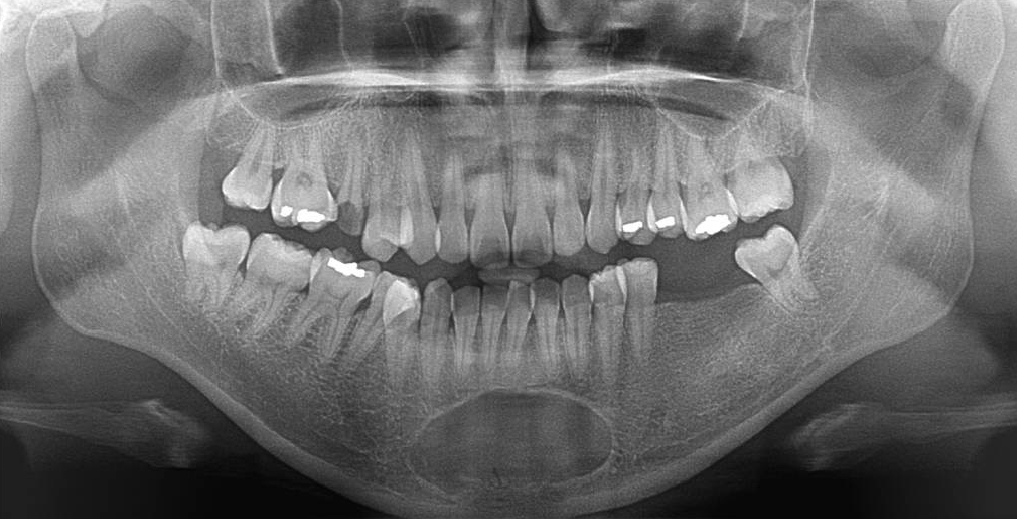

Figure 1.

Panoramic view. A well-defined, corticated, oval-shaped radiolucency was observed in the periapical region of the mandibular right to left first premolars on panoramic radiography.

32세 여성 환자의 파노라마방사선영상에서 하악 전치부 낭이 관찰되어, 정확한 진단을 위하여 본원에 의뢰되었다. 특별한 임상증상은 없었다. 파노라마방사선영상에서 하악 우측 제1소구치에서 좌측 제1소구치 치근하방에 경계가 명확하고 피질골성 변연을 가진 타원형의 방사선투과상이 관찰되었다(Fig. 1). 방사선투과상은 해당치아들과는 무관하여 치근단낭이 배제되었고, 단순골낭의 가능성을 염두에 두고 콘빔CT 검사를 시행하였다. 콘빔CT에서 중심성 골내 병소가 아닌 악골의 순측에서 설측으로 함몰된 변연성 병소가 관찰되었다(Fig. 2). 병소의 경계는 매우 평활하였고, 단면상에서는 넓은 접시모양처럼(Fig. 3), 악골 절단면상에서는 반달모양처럼 함몰되어 있었다(Fig. 4). 설측 피질골은 비박되어 있었으나 천공은 관찰되지 않았다. 함몰된 부위는 공기가 아닌 연조직의 방사선투과상으로 채워졌으나, 콘빔CT에서는 대조도가 낮아서 연조직간의 감별이 가능하지 않았다(Fig. 5). 관찰된 턱 끝 부위의 골 함몰이 해부학적 변이인지 아닌지를 감별하기 위하여 환자의 과거 병력을 알아보았다. 환자는 2년 전에 턱 끝 부위에 미용 필러 시술을 받았다고 하였다. 방사선영상소견과 문진결과를 토대로, 미용 필러와 관련된 골흡수를 의심하였다. 이후 외과적으로 미용 필러 제거와 함몰된 부위에 골이식이 시행되었다. 수술 중에 육안으로 남아있는 미용 필러와 작은 석회화 물질들이 확인되었다. 수술 후 생검에서 다핵거대세포와 결절석회화가 관찰되었고, 피부석회화(calcinosis cutis)가 의심된다는 결과를 받았다. 이상의 술 전 검사 및 술 후 소견을 종합하여, 파노라마방사선영상에서 관찰된 방사선투과상은 치성낭이나 해부학적 변이가 아니고 미용 필러에 의한 하악골 순측 골흡수로 최종 진단되었다.